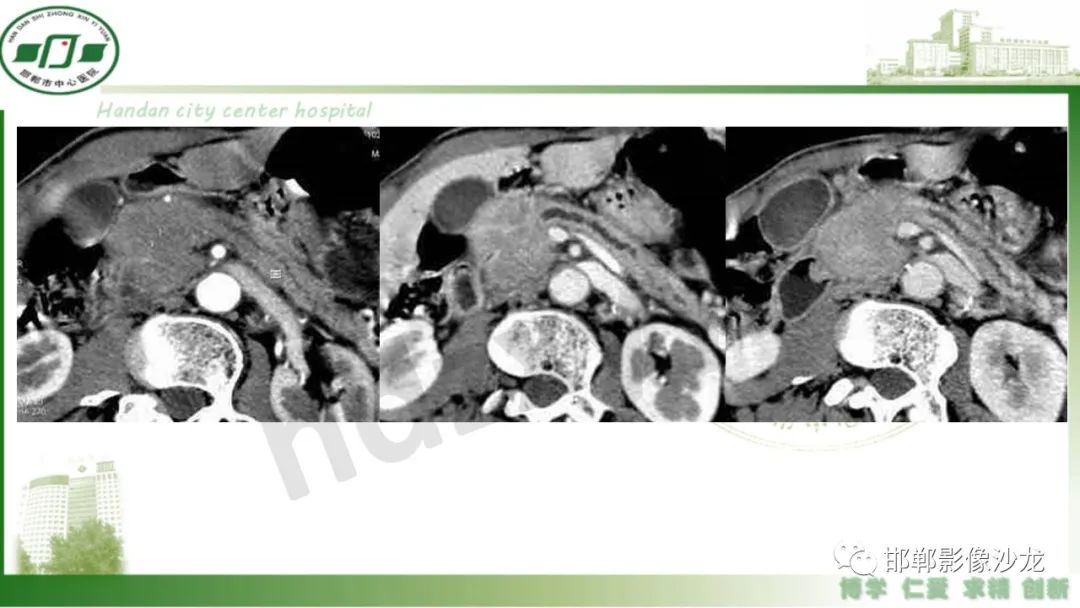

【PPT】肿块性胰腺炎

肿块性胰腺炎与胰腺癌的临床、实验室检查、影像学表现有时候很难鉴别,但两者的临床处理、预后又有很大的不同,因此我们平时工作中需要注意两者之间的区别,谨慎诊断,力争为患者及临床带来更大的帮助。